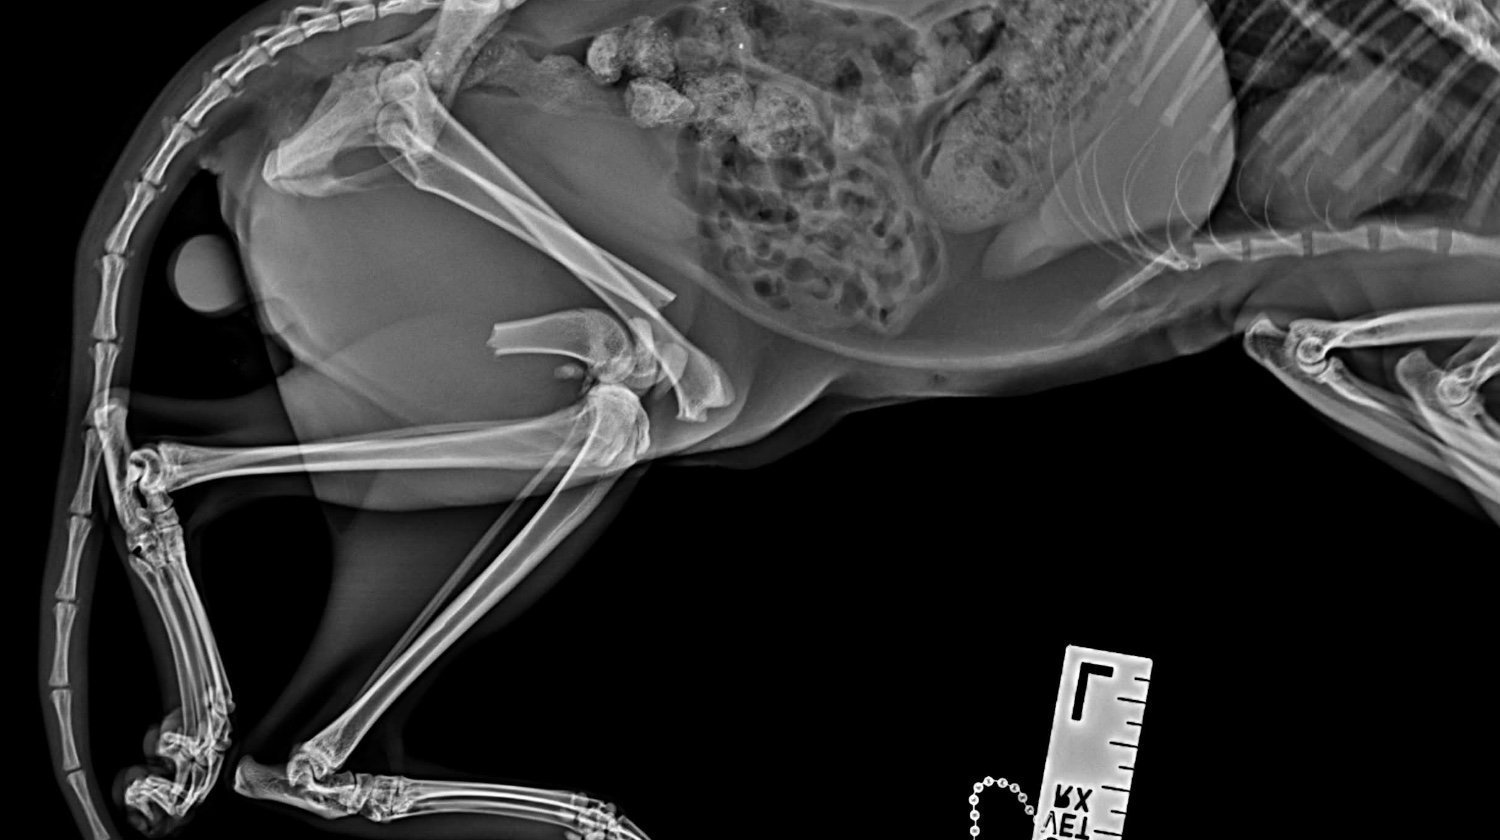

Lucky je maček, ki so ga pred nekaj dnevi našli pred blokom, v katerem živi moj brat. Luckyja je takoj odpeljal k veterinarju. Po posvetu je ugotovil, da ima poškodovani obe nogi in medenico :(. Natančneje, ima naslednje težave:

Medenica

obojestranska sakroiliakalna dismoreksija

Zlom desne iliakalke s premikom

Zadnje okončine

Diafizni zlom v srednji tretjini, poševni, s premikom, brez kostne eklatantnosti, na ravni stegnenice femurulolistangii

Zlom tipa SH I distalno od desne stegnenice

Slikovna diagnoza: zlom leve stegnenice, SH zlom desne stegnenice, obojestranski križno-iliakalni izpah, zlom desne iliakalne palete

Po opravljenih rentgenskih posnetkih, kjer so bile ugotovljene

zgoraj, so ga odpeljali k ortopedu in bo potreboval 3 operacije: po eno za vsako nogo + operacijo medenice.